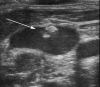

Central venous access is increasingly becoming the domain of the radiologist, both in terms of the insertion of central venous catheters (CVCs) and in the subsequent management of these lines. This article seeks to provide an overview of the CVC types available for paediatric patients and a more detailed explanation of the spectrum of complications that may lead to catheter malfunction. A standard catheter contrast study or 'linogram' technique is described. The normal appearances of such a study and a detailed pictorial review of abnormal catheter studies are provided, together with a brief overview of how information from catheter investigations can guide the management of catheter complications.